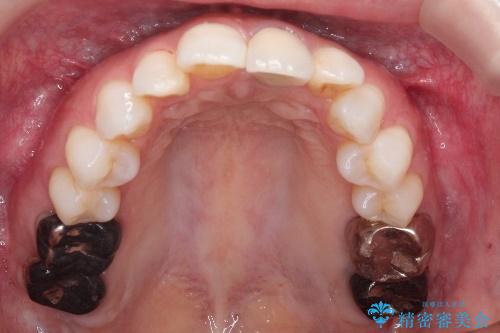

インビザラインによる非抜歯矯正 ガタガタな歯並びを整った歯並びへ

- 上下の全体的ながたつきが気になるとのことで来院されました。

マウスピースでの目立たない矯正を希望されたので、インビザラインでの治療となりました。

全体的に歯と歯の間にわずかに隙間を作り、歯を並べました。